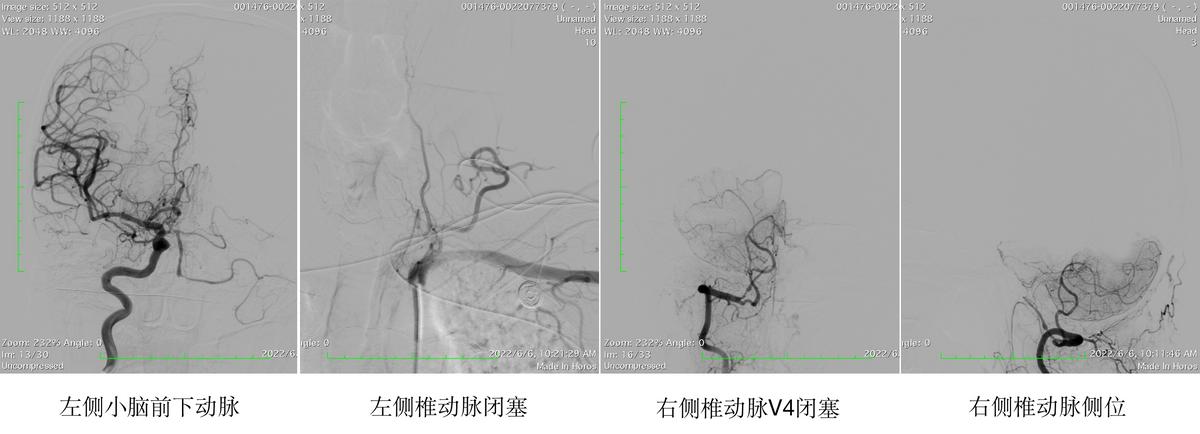

患者男性,56岁,因头晕伴右侧肢体无力1年余入院,于外院行全脑血管造影术,诊断为左侧椎动脉全程闭塞,右侧椎动脉V4段闭塞,后尝试行右侧椎动脉闭塞再通术,未再通成功。5月25日,患者联系到哈医大一院群力神经外科主任史怀璋教授,希望能够得到治疗。

在详细讨论手术方案后,史怀璋教授与郑秉杰副教授手术团队选择了枕动脉-小脑前下动脉搭桥术治疗。后循环搭桥手术目前在国内只有少数几个顶级神经外科中心开展,我省暂无将后循环搭桥手术应用于缺血性疾病。